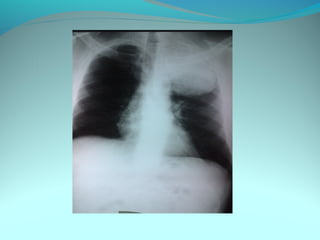

Opacité occupant la partie externe du 1/3 infer du poumon droit

dense et homogene ovalaire de 8cm de grand axe vertical

La limite externe se confend avec une opacité d’environ 1cm comble

les coupole costodiaphragmatique droit

Limitée a sa partie sup par la petit sessure qui est epaisse et pas de

lyse costale

 DIAGNOSTIC :DIAGNOSTIC :

 1_1_cancer bronchique droit( d epaississement)

 2_2_ kyste hydatique au stade sain